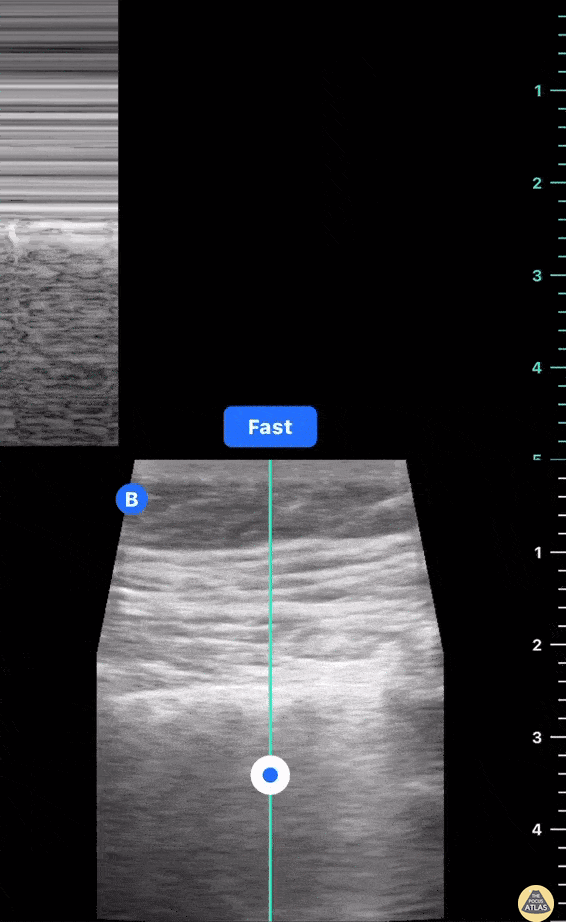

Lung Sliding with M mode; looking like a seashore. Mary Fran King

https://www.thepocusatlas.com/lung